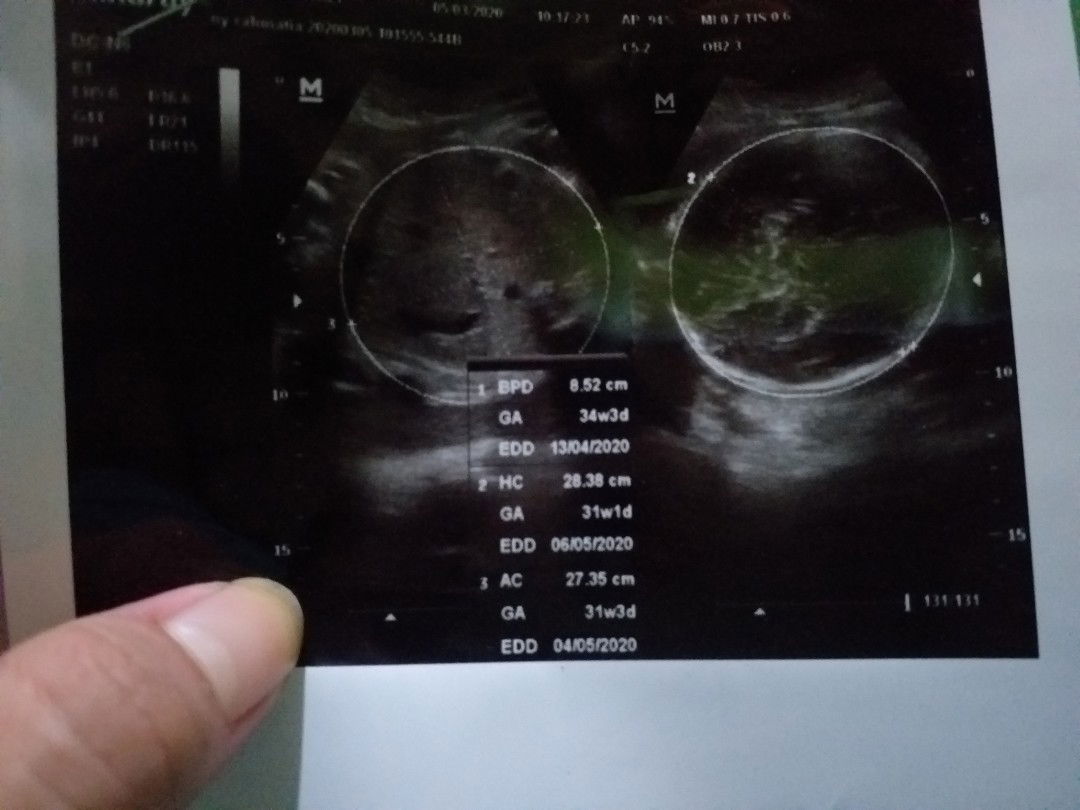

cara cepat naikin BB janin?

Bunda mau nanya dong , gimana cara naikin bb janin dengan cepat? Soalnya kemarin sudah USG tapi kata dokter bayinya kecil cuma 2 kg padahal udah 8 bulan? hpl 13 april 2020